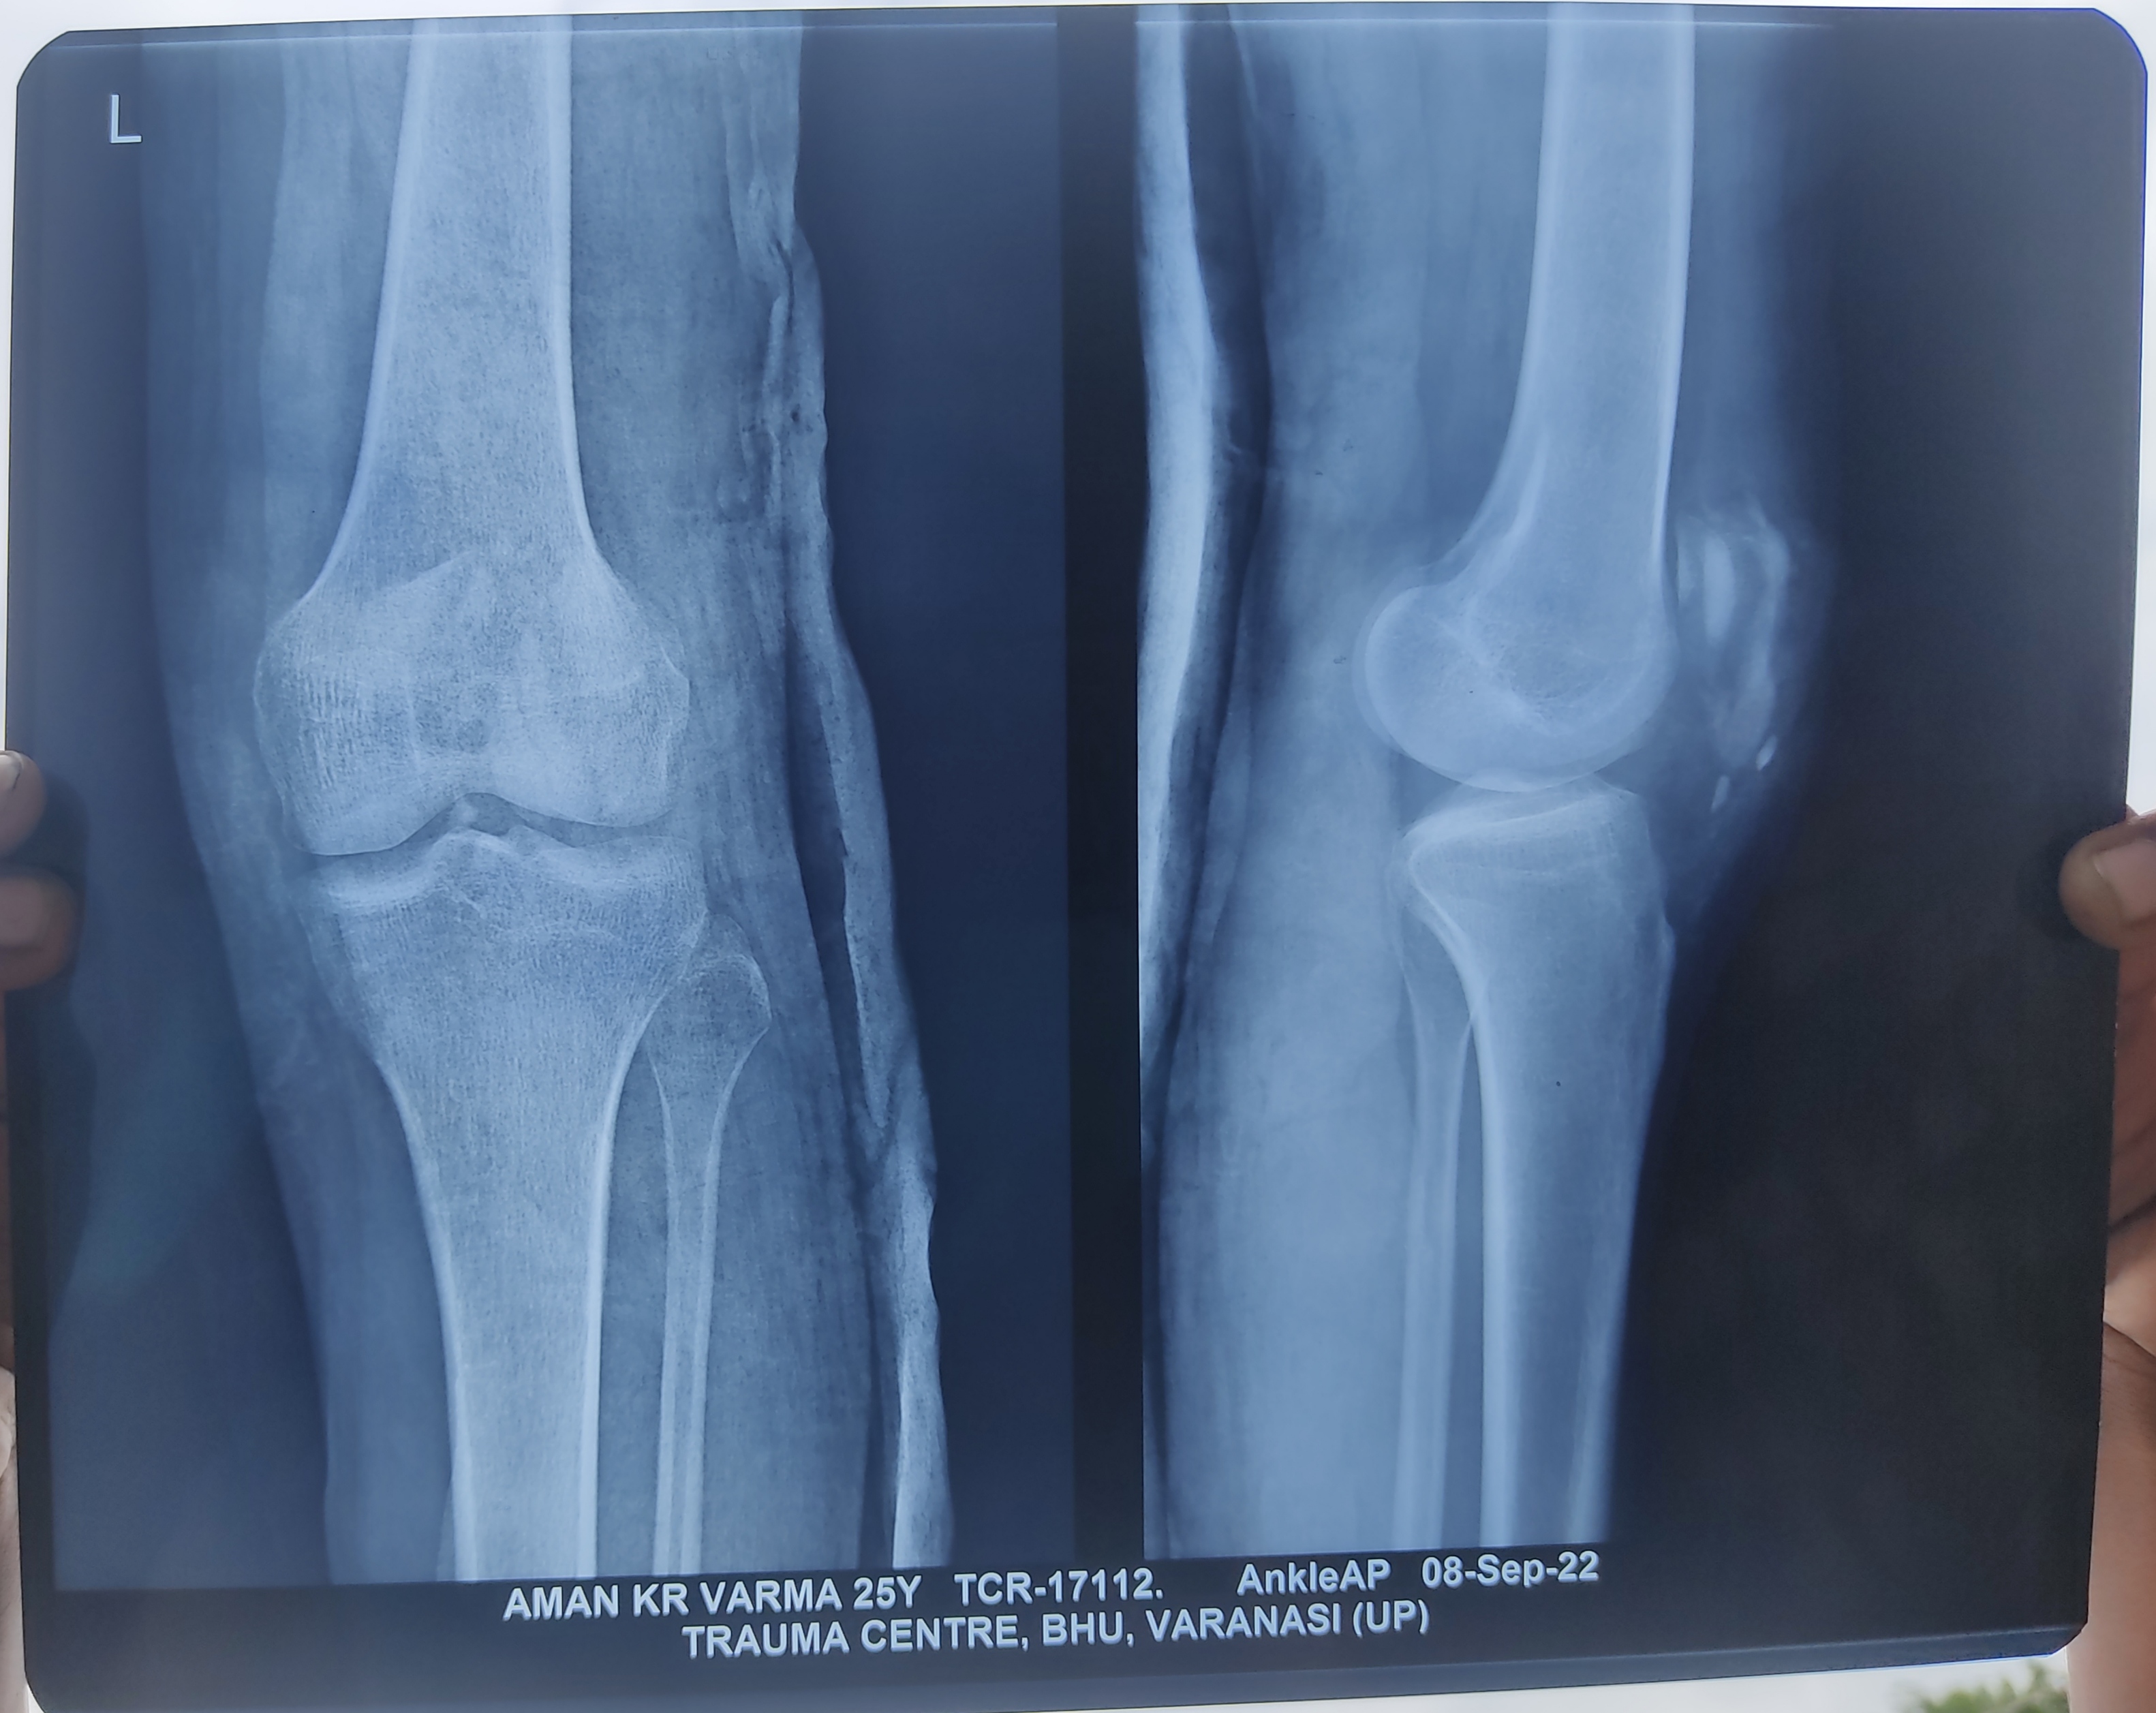

सर मेरा accident 25 अगस्त को हुआ था BHU TRAUMA CENTER (VARANASI) मे हो रहा है 9 टाके लगे थे मेरे घुटने पर 1 महीना 10 दिन हो गया लेकिन मेरा पैर मुड़ नहीं रहा है अभी आपरेशन भी नहीं हुआ हैं डॉक्टर भी सही गाइड नहीं कर रहे है मुझको मैं खड़ा नहीं हो पा रहा , खड़ा होता हूँ तो पैर कांपने लगता है यहाँँ पर मुझको कोई उम्मीद नहीं दिख रही है exercises भी कर रहा कुछ नहीं हो रहा 10 डिग्री मुड़ रहा हैं केवल आप ही मेरी आखिरी उम्मीद है सर please mera pair mod dijiye please??

Sir mera MRI nhi hua h aur chal nhi pata jra bhi mai chot ka foto bhi bhej rha hu

Vedio , aur pdf k sath xray bheja hu whatsup no pr thod dhyan de dijiye please

Isme aap time kharab na kare . Sabse pahle 3 Tesla MRI karwaye Takee pata lage ki koi ligament ka problem to nahee hai . Uske baad aage decision le . Aap mujhe mri bhej bhee sakte hain